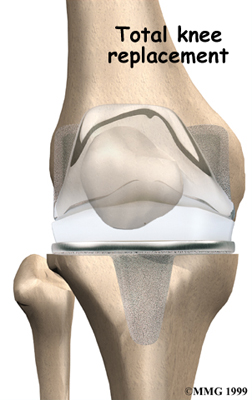

Artificial Knee Replacement

An artificial knee replacement is the ultimate solution for advanced knee OA.

Surgeons prefer not to put a new knee joint in patients younger than 60. This is because younger patients are generally more active and might put too much stress on the joint, causing it to loosen or even crack. A revision surgery to replace a damaged prosthesis is harder to do, has more possible complications, and is usually less successful than a first-time joint replacement surgery.

Related Document: FYZICAL South Green Valley's Guide to Artificial Joint Replacement of the Knee